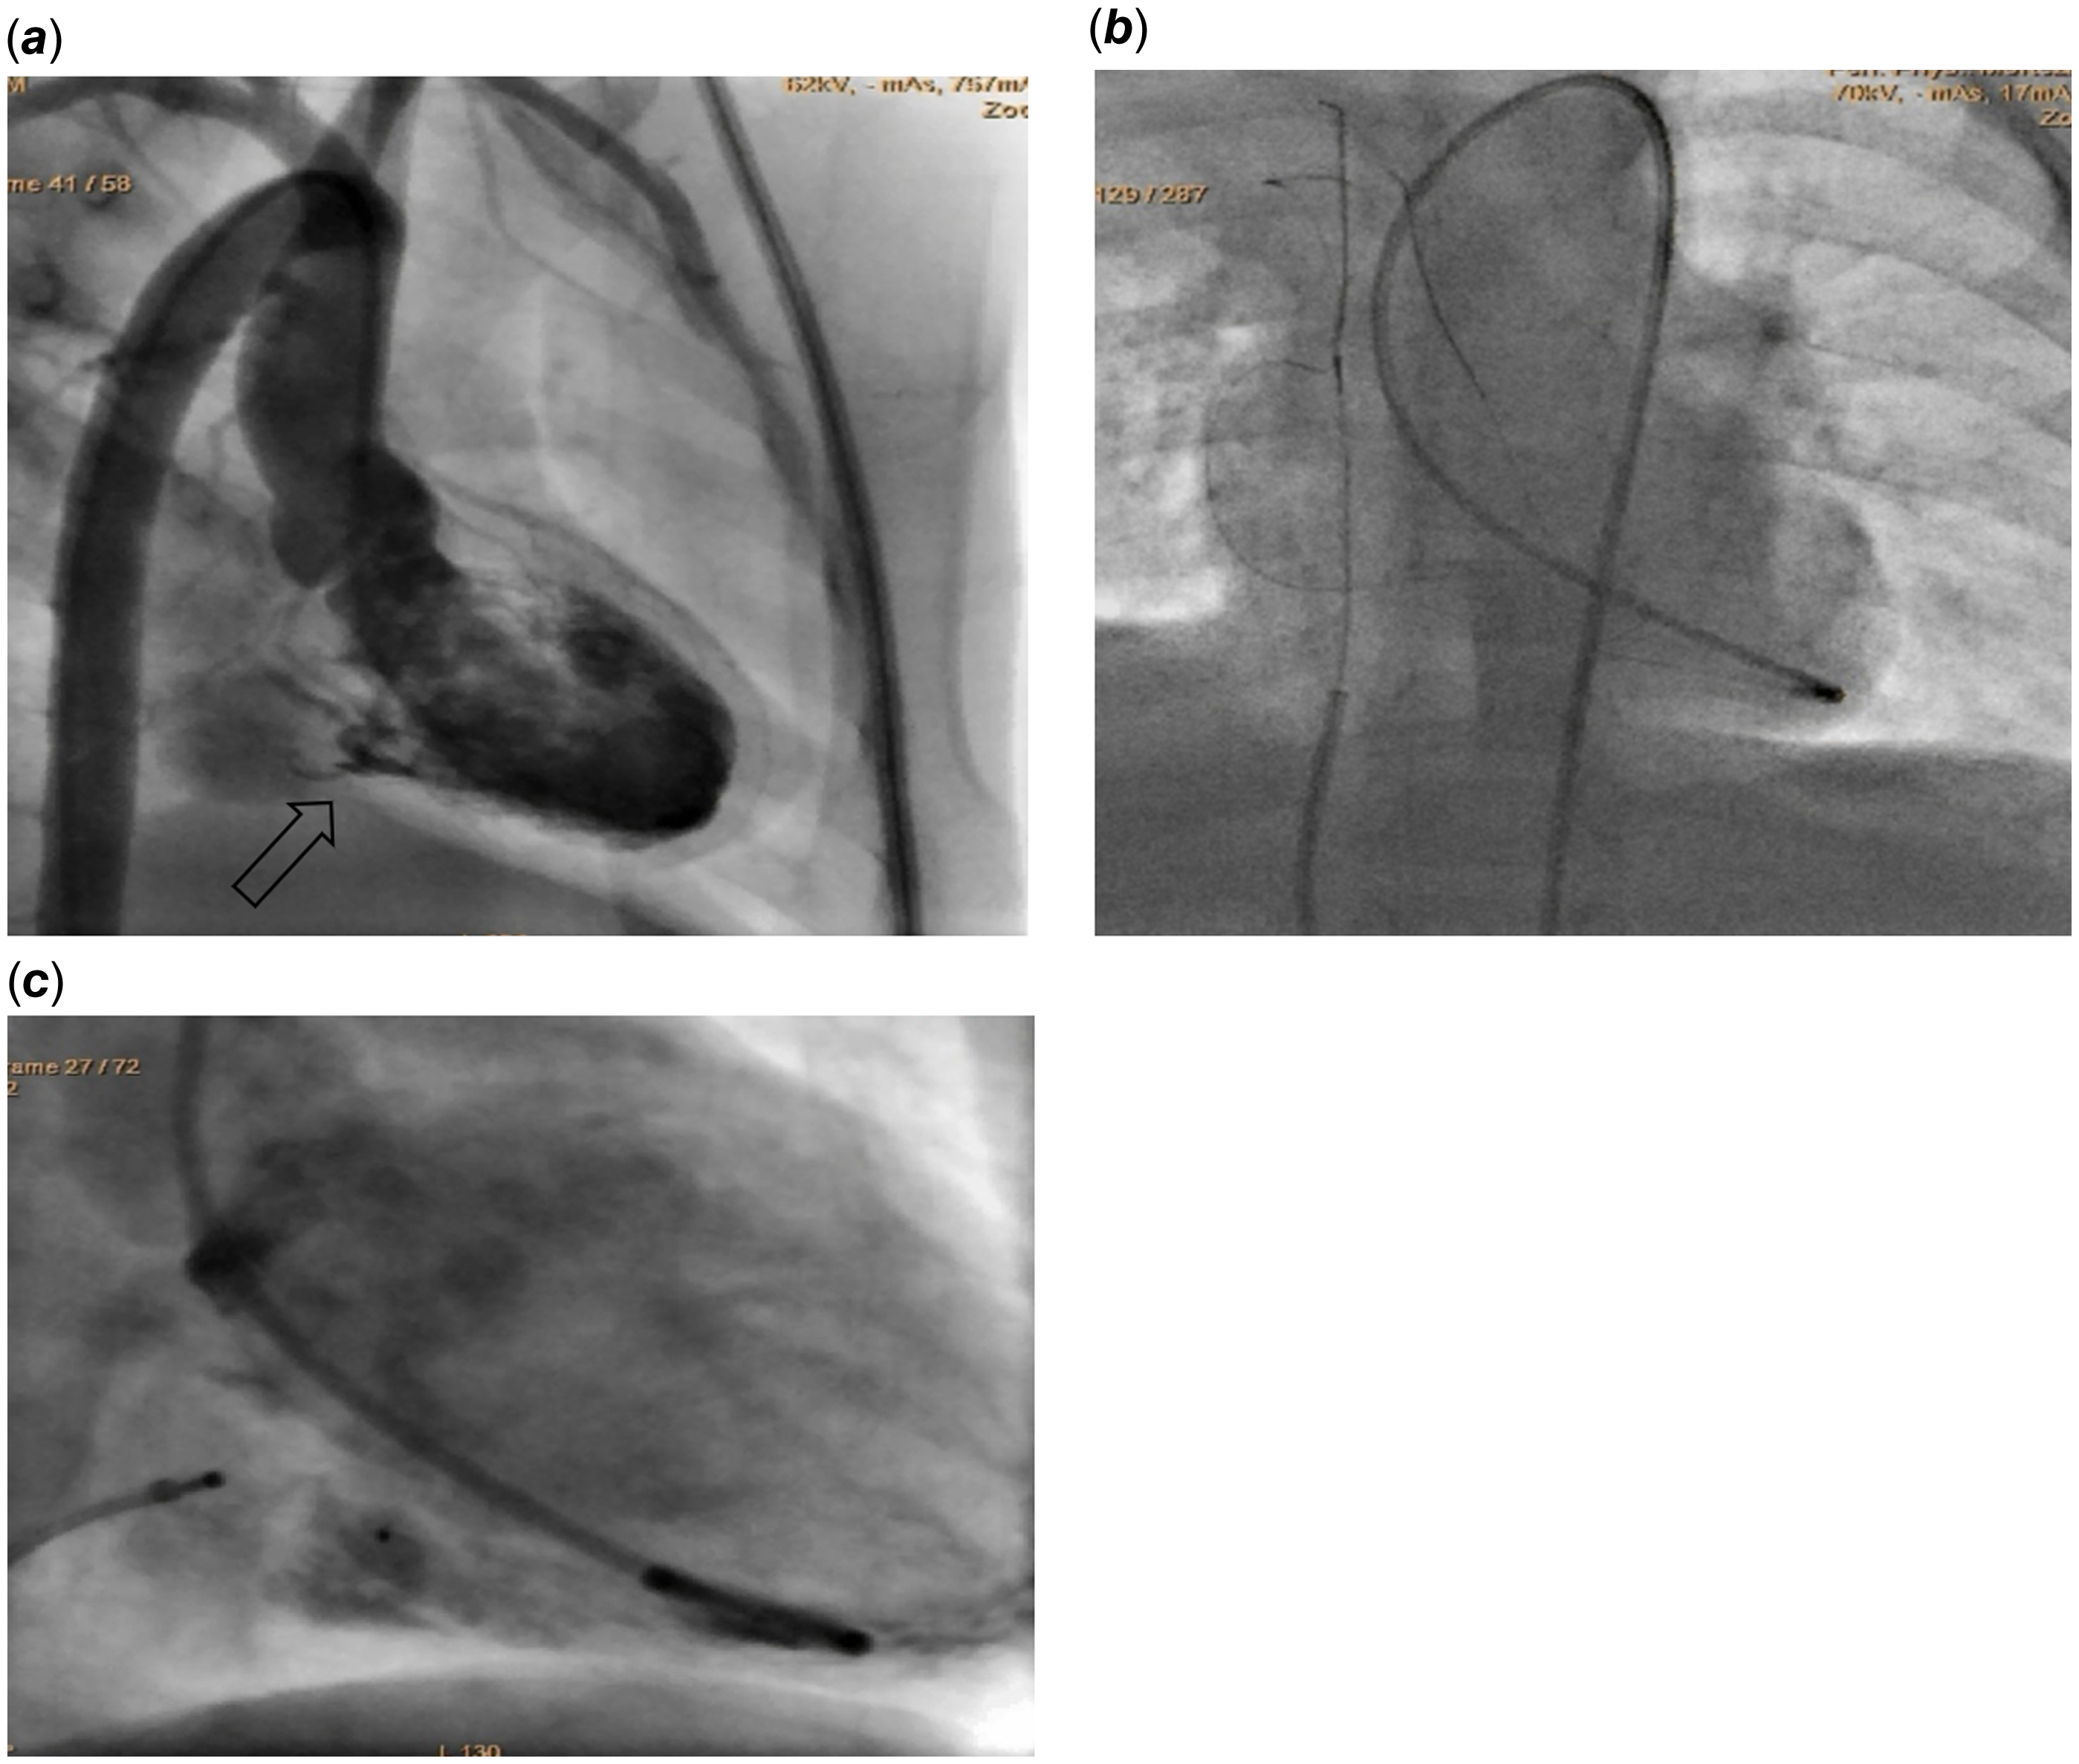

We report the case of an 18-month-old male, born full-term at 40 weeks without neonatal complications. At admission, his weight was 12 kg. The patient was acyanotic and asymptomatic. Cardiac examination revealed a prominent 3/6 systolic ejection murmur; however, there were no signs of heart failure or organomegaly, and weight gain was normal. Chest radiography indicated slight cardiomegaly, while the electrocardiogram showed sinus rhythm with a normal axis and no ST or T wave changes. A 2D and Doppler echocardiogram identified a dilated coronary sinus due to a left ventricular to coronary sinus fistula, with a jet waist measuring 3 mm and velocity around 4 m/sec. The pressure gradient across the fistula was noted at 60 mm Hg (Figure 1). Additionally, moderate right atrial enlargement and right ventricular enlargement were observed, with an Left Ventricular Ejection Fraction of 60%. Pre-procedural CT angiography provided a detailed anatomical evaluation, showing a width of 3 mm and a length of 4 mm (Figure 2). Catheterization revealed normal right atrial pressure and pulmonary artery pressures of 30/15 mmHg (mean 22 mmHg). Oxygen saturation levels indicated a significant left-to-right shunt with Qp/Qs of 1:1.5. Two catheterisation strategies, antegrade and retrograde, were evaluated for the occlusion procedure. Due to the intricate anatomical structure and the demanding wire-snaring location, the antegrade approach was favoured. This strategy facilitated traversal through the defect from the left ventricle to the coronary sinus, with successful snaring executed in the right atrium. In contrast, utilizing the retrograde approach would have necessitated wire snaring within the left ventricle, which was anticipated to be more challenging than the antegrade method. To close this fistula, a 4 French pig-tail catheter, which had been appropriately sized by trimming its tip, was first inserted into the left ventricle via the femoral artery. Subsequently, a 0.018-inch guidewire was used to traverse the fistula, and the wire was snared in the right atrium. After successfully navigating the fistula pathway, it was occluded using a Piccolo device (5 mm × 4 mm). The selection of this device was due to its optimal flexibility and the ability to conform to the anatomical configuration of the lesion. To ensure precise placement and maximum stability, the first disc of the device was positioned in the left ventricle, the body of the device within the fistula, and the final disc in the coronary sinus. Given the enlarged and dilated nature of the coronary sinus, positioning the edge of the device at the base of the coronary sinus did not interfere with the sinus pathway (Figure 3). Serial echocardiographic follow-ups before discharge and at 1, 6, 12, 24, and 32 months post-procedure showed minimal residual shunt initially, which resolved completely in subsequent studies with no shunt present at the fistula site (Figure 4). A 24-hour Holter monitor post-discharge confirmed normal sinus rhythm without ectopic beats or arrhythmias.

Figure 2. (a, b) An axial plane showing a dilated coronary sinus with a connection to the left ventricle (c) In the sagittal plane demonstrated the insertion of a fistula into the coronary sinus.

Figure 3. (a) Cineangiogram image, captured in the Right Anterior Oblique (RAO) view, demonstrates an injection that reveals a dilated coronary sinus in relation to the left ventricle (LV) (b) catheter was introduced via the right femoral artery to the LV, and a 0.018-inch guidewire was inserted into the coronary sinus, extending from it into the superior vena cava (SVC) where the guidewire was subsequently snared (c) Device adjustment and successful closure of a defect.